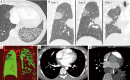

Acquired pulmonary vein stenosis (PVS) is an uncommon occurrence in adults, but one that carries significant morbidity/mortality. PVS can be secondary to neoplastic infiltration/extrinsic compression, non-neoplastic infiltration/extrinsic compression, or iatrogenic intervention. This article: (I) reviews the common causes of acquired PVS; (II) illustrates direct and indirect cross-sectional imaging findings in acquired PVS (in order to avoid misinterpretation of these imaging findings); and (III) details the role of imaging before and after the treatment of acquired PVS.